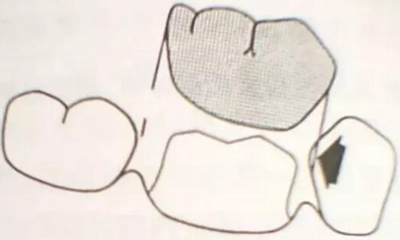

牙體解剖知識(shí)

牙體各個(gè)面的解剖厚度